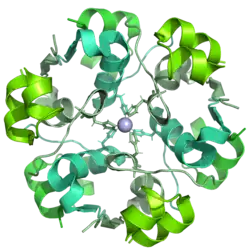

Insulin aspart

Insulin aspart, marketed under the brand name Novolog among others, is a modified type of medical insulin used to treat both type 1 and type 2 diabetes.[38] It is typically administered by injection under the skin (into the abdomen, buttocks, thighs, or upper arms), but can also be injected into a vein.[39] Its maximum effect occurs after about 1–3 hours and lasts for 3–5 hours.[40] A biosimilar version of insulin aspart, insulin-aspart-szjj, was released in 2025.[41]

Common side effects include low blood sugar, allergic reactions, itchiness, and pain at the injection site. Serious side effects may include low blood potassium.[38] It is generally considered safe to use during pregnancy and breastfeeding.[42][38] It works similarly to human insulin by enhancing glucose uptake in tissues and reducing glucose production by the liver.[38] It is a synthetic form of human insulin, with a single amino acid change, replacing proline with aspartic acid at the B28 position.[43]

Insulin aspart was approved for medical use in the United States in 2000.[44] In 2022, it was the 76th most commonly prescribed medication in the United States, with over 8 million prescriptions.[28][45] Its production involves yeast that have had the gene for insulin aspart inserted into their genome, allowing the yeast to produce the insulin, which is then harvested from the bioreactor.[46][47] Insulin aspart is available unbranded from Novo Nordisk.[15][16]